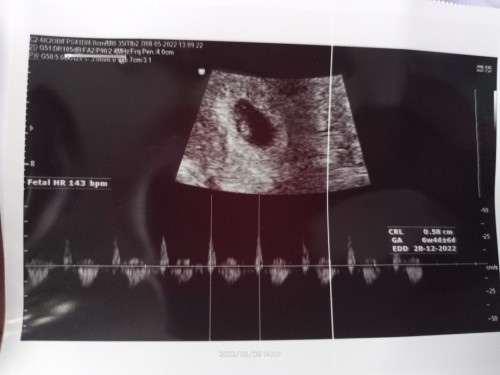

Hasil USG saat usia kehamilan 6 minggu.ini udah terlihat janin nya atau belom ya.

Maaf ada yg tau ga ya??Saat USG saking seneng nya dokter ngomong aku ga dengerin bgt..cm dengernya udah ada kantong nya pas ngomong janin aku g denger Krn dah keburu seneng penantian 11 Thn pengen USG LG tapi jadwal kontrol bulan depan.dan skrg LG wory bgt Krn sering liat status org² hamil BO jd takut...#seriusnanya